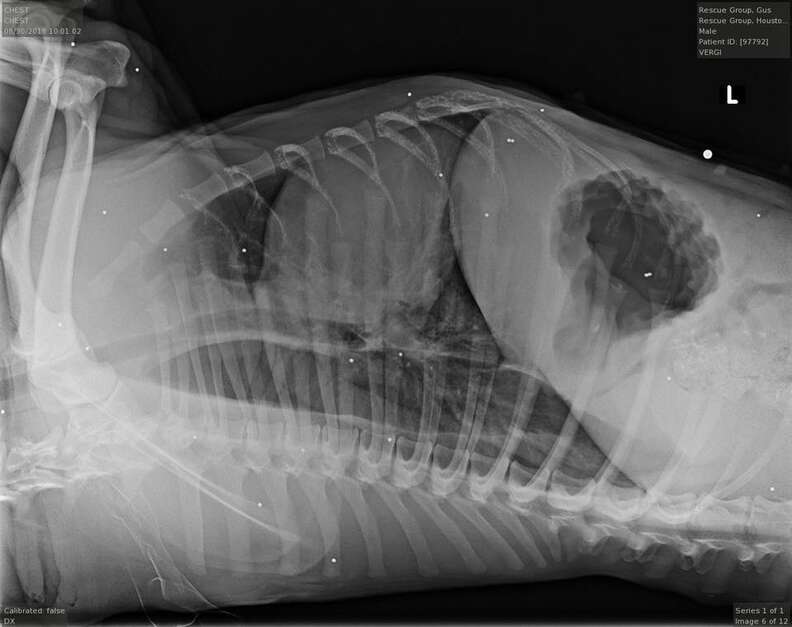

X-rays revealed a horror show inside his small body. His pelvis was shattered—evidence of being hit by a car and left to suffer. And scattered across his legs and ribs were 26 pellets.

Someone had used Gus for target practice. Twenty-six times.